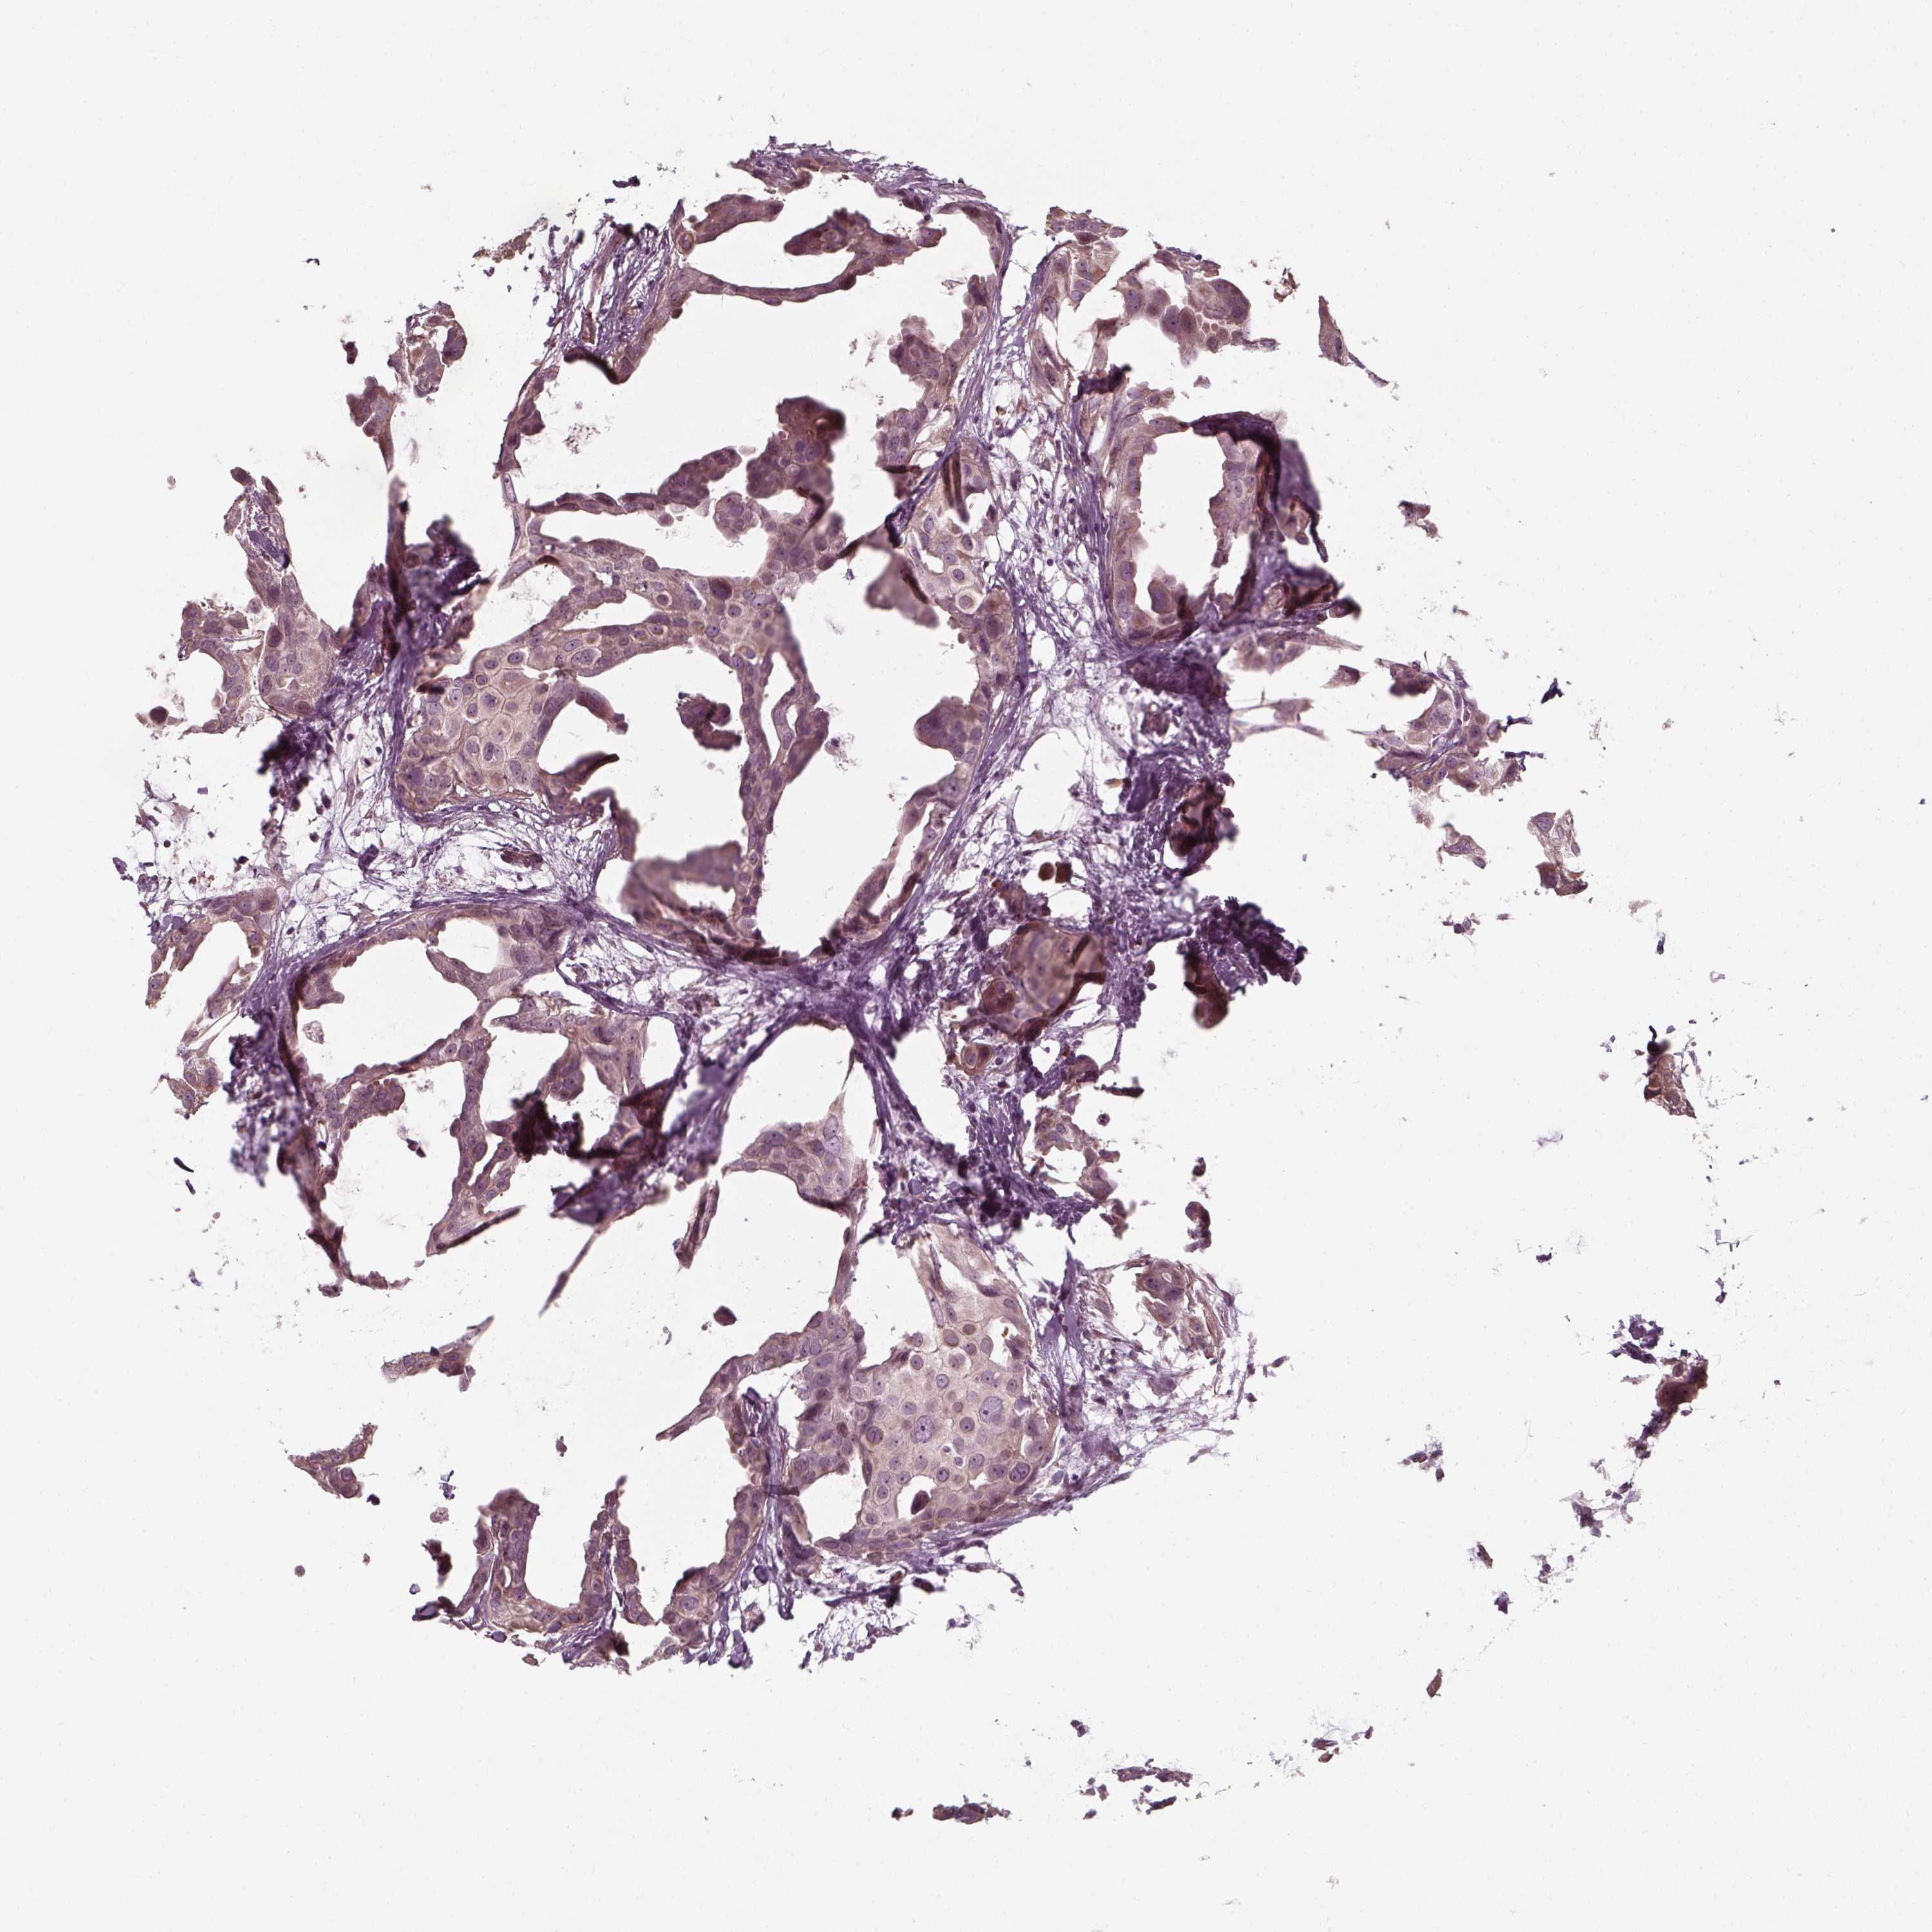

CANCER BREAST CANCER Show tissue menu

BRCA TCGA BRCA VALIDATION PROTEIN EXPRESSION

Breast cancer

Human cancer